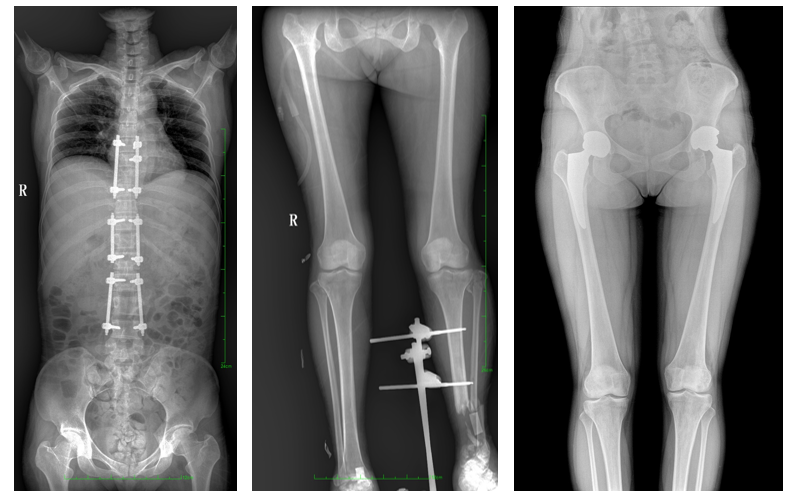

DR常用于人體胸部及骨骼攝片,也可拍攝其他部位,例如腹部、牙齒、頭顱等。使用人群較廣,可以進(jìn)行全身各部位檢查,曝光后幾秒就可獲得數(shù)字影像,成像速度快,且價格便宜,極大提高了工作效率,方便臨床重癥、急癥患者的診治。

站立位X線影像是測定人體負(fù)重骨骼的生物學(xué)力線、對稱結(jié)構(gòu)平滑線及脊柱側(cè)凸角等首選的檢查內(nèi)容,這和CT、MRI臥位成像,在臨床意義上有著根本區(qū)別。在脊柱及下肢的臨床治療過程中,一般需要進(jìn)行矯正和關(guān)節(jié)置換手術(shù)治療,在對其進(jìn)行手術(shù)前后,均需要拍攝站立位負(fù)重X光片以便分析病情,明確診斷和觀察治療效果。

常規(guī)DR拍攝面積有限,最大規(guī)格僅有43cm,但成人男性全脊柱長度平均為70-75cm,女性為66-70cm,而雙下肢更長。普愛醫(yī)療PLX8600動態(tài)DR的43cm*86cm超大有效視野,可一次成像全脊柱及雙下肢。